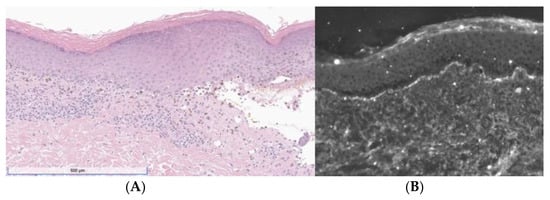

A 46-year-old woman presented with a 3-week history of painful and pruritic blisters. Her pertinent past medical history includes an 8-month history of metastatic adrenocortical carcinoma, for which she was initially treated with six cycles of etoposide, doxorubicin, and cisplatin plus oral mitotane chemotherapy that was complicated by neuropathy. She was subsequently treated with four cycles of pembrolizumab, a PD-1 inhibitor. Hives and angioedema developed 11 days after the first dose of pembrolizumab, which resolved with oral antihistamines. She went on to receive three additional doses; however, pembrolizumab was discontinued after the fourth dose, as her metastatic disease had progressed. One week after her final infusion of pembrolizumab, the patient simultaneously developed tense bulla and pruritic plaques of the trunk and extremities. The physical exam was notable for diffuse lichenoid plaques and tense bullae on the chest, abdomen, and extremities with the greatest disease burden affecting the lower extremities (Figure 1). The exam was negative for oral mucosal findings like Wickham striae. A biopsy taken from the right thigh demonstrated subepidermal separation with a patchy dermal lymphocytic infiltrate, basilar dyskeratosis, necrosis, and presence of rare eosinophils (Figure 2A). Direct immunofluorescence (DIF) exhibited linear deposition of IgG and C3 along the basement-membrane zone (Figure 2B). The collective clinical, histopathologic, and immunofluorescence findings were consistent with a diagnosis of LPP. The patient was treated with topical and oral steroids, and the condition improved over a 3-month follow-up period without sequelae.

Figure 2. (A) H&E showing band-like lymphocytic infiltrate with vacuolization of the basal layer, necrotic keratinocytes, pigment incontinence, and a subepidermal split. (B) DIF was positive for linear deposition of IgG (depicted) and C3.

Histopathologic and immunofluorescence findings are highlighted in Table 3. Band-like lichenoid dermatitis was identified in all cases, often accompanied by basal-layer vacuolization (55%, 11/20), hyperkeratosis (55%, 11/20), lymphocytic infiltrate at the dermal–epidermal junction (45%, 9/20), and dyskeratotic keratinocytes (45%, 9/20). Subepidermal blisters were reported in 15 cases (75%) and eosinophilic infiltrate was observed in 10 cases (50%). DIF revealed linear C3 or IgG deposition for 95% of patients (18/19), with 68% (13/19) presenting with both C3 and IgG deposition. Four cases (21%) reported only a positive C3 deposition, and one case (5%) was positive for a linear IgG deposition at the dermal–epidermal junction. One case had negative DIF findings, but indirect immunofluorescence (IIF) demonstrated a weak linear IgG deposition at the basement-membrane zone on monkey esophagus. Another case revealed a DIF finding of fibrinogen along the basement-membrane zone. This finding, while not frequently reported in the reviewed cases of LPP, has been independently associated with both LP and BP [24,25].